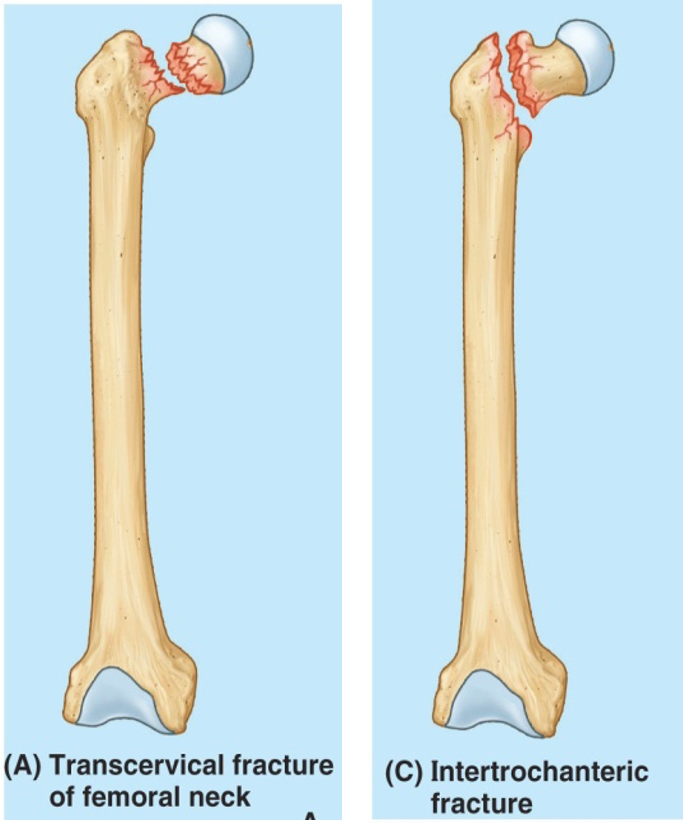

most common hip fx?

femoral head fx

80% occur in women secondary to a fall

Intracapsular (head and neck)

Subject to avascular necrosis and non-union

Intertrochanteric fractures

Anatomy:

Extracapsular

Good cancellous bone

Highly vascular

Abundant blood supply

Displaced-shortened and externally rotated